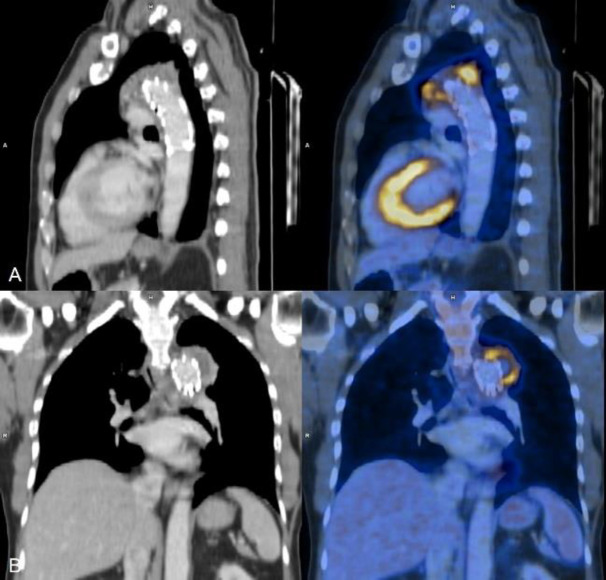

随着介入心脏病学手术数量的增加,心脏设备感染(包括起搏器、人工瓣膜、冠状动脉和主动脉支架)的数量也在增加。这些感染会导致严重的发病率,如果处理不及时甚至会导致死亡。如果临床上怀疑有心脏装置感染,第一线影像检查方法是经胸超声心动图,经食道超声心动图也可用于特定病例。心脏设备感染的确诊大多需要借助血液或脓液培养。尽管超声心动图是一种非常有效的心脏评估技术,但它无法区分感染与血栓或纤维化。随着正电子发射计算机断层扫描(PET CT)机在全球范围内的普及,18F-FDG PET CT 在感染成像中的应用越来越受到重视,尤其是在心脏设备感染方面。最近的大多数研究表明,18F-FDG PET CT 具有良好的诊断准确性,许多最新的诊断和管理指南都承认了它的作用,尤其是在诊断不明确的病例中。我们介绍了六个这样的病例,在这些病例中,18F-FDG PET CT 为疑似心脏设备感染患者的诊断、确诊感染的存在、划定感染范围、治疗反应,有时甚至帮助做出适当的治疗决策提供了有价值的信息。

With the increasing number of interventional cardiology procedures, the number of cardiac device infections (including pacemakers, prosthetic valves, coronary and aortic stents) have also increased. These infections can cause significant morbidity and can even lead to mortality if not managed promptly. If suspected clinically the first-line imaging modality is Trans-Thoracic Echocardiography, while Transesophageal Echocardiography is also used in selected cases. The confirmation of a cardiac device infection is mostly done with the help of blood or pus culture. Even though Echocardiography is a very efficient technique for the evaluation of the heart, it cannot differentiate infection from thrombus or fibrosis. With the increasing availability of Positron Emission Tomography CT (PET CT) machines worldwide, the use of 18F-FDG PET CT for infection imaging has gained traction, especially for cardiac device infection. Most of the recent studies show a good diagnostic accuracy of 18F-FDG PET CT with many of the recent diagnostic and management guidelines now acknowledging its role, especially in equivocal cases. We present six such cases where 18F-FDG PET CT provided valuable information either for diagnosis, confirming the presence of infection, delineating extent, therapy response or sometimes even helping appropriate treatment decision making in patients with suspected cardiac device infection.